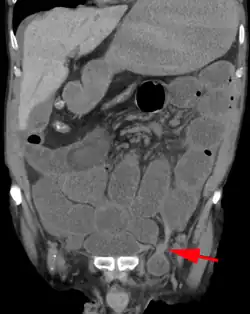

Medical imaging

A physician may diagnose an inguinal hernia, as well as the type, from medical history and physical examination.[20] For confirmation or in uncertain cases, medical ultrasonography is the first choice of imaging, because it can both detect the hernia and evaluate its changes with for example pressure, standing and Valsalva maneuver.[21]

When assessed by ultrasound or cross sectional imaging with CT or MRI, the major differential in diagnosing indirect inguinal hernias is differentiation from spermatic cord lipomas, as both can contain only fat and extend along the inguinal canal into the scrotum.[22]

On axial CT, lipomas originate inferior or lateral to the cord, and are located inside the cremaster muscle, while inguinal hernias lie anteromedial to the cord and are not intramuscular. Large lipomas may appear nearly indistinguishable as the fat engulfs anatomic boundaries, but they do not change position with coughing or straining.[22]